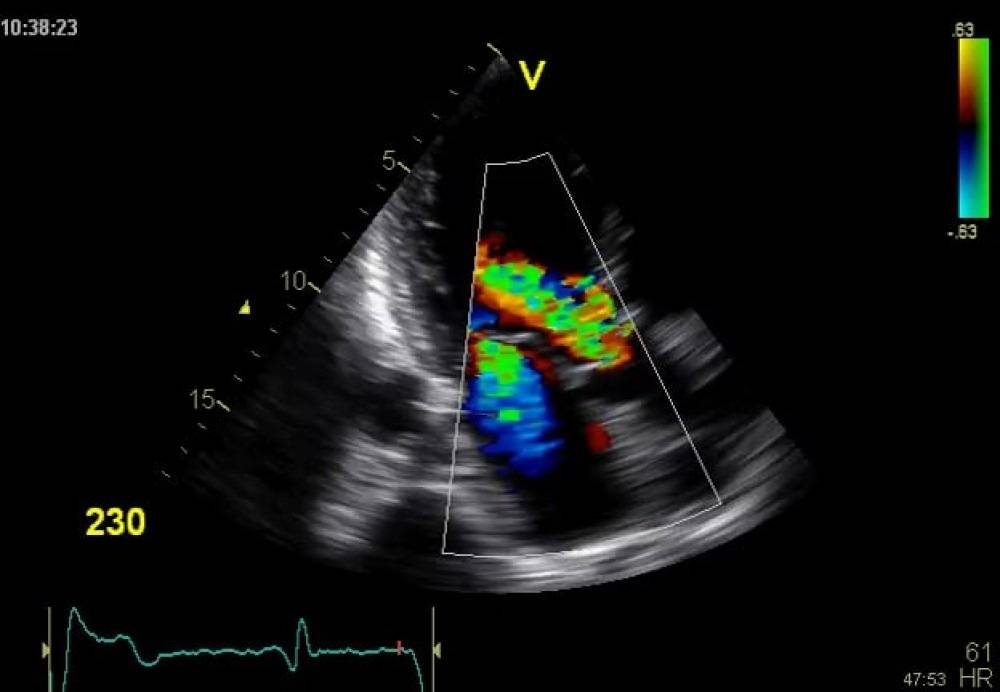

ارزیابی جریان خون جفت و جنین (میانگین جریان مغزی، جریان شریان نافی، جریان شریان های رحمی) با سونوگرافی داپلر رنگی

سونوگرافی داپلر رنگی ابزار ارزشمندی است که در دوران بارداری برای ارزیابی جریان خون جنین در حال رشد، جفت و سایر ساختارهای مادر استفاده می شود. این تکنیک تصویربرداری غیر تهاجمی اطلاعات مهمی در مورد گردش خون ارائه می دهد و می تواند به تشخیص عوارض احتمالی کمک کند. در اینجا آنچه شما باید در مورد سونوگرافی داپلر رنگی در بارداری بدانید، از جمله آماده سازی و آنچه که باید انتظار داشته باشید، آورده شده است.

نظارت بر جریان خون: در طول سونوگرافی داپلر رنگی، سونوگرافیک به طور خاص بر روی الگوهای جریان خون در رحم، جفت و بند ناف تمرکز می کند. آنها تصاویر رنگی را برای ارزیابی جهت، سرعت و کیفیت جریان خون تجزیه و تحلیل خواهند کرد.

سونوگرافی داپلر رنگی در بارداری یک ابزار تشخیصی ارزشمند است که به نظارت بر سلامت جنین و تشخیص عوارض احتمالی کمک می کند. با ارزیابی جریان خون جنین و جفت، اطلاعات حیاتی برای مدیریت بارداری های پرخطر ارائه می کند. از طریق آماده سازی مناسب و درک آنچه که باید انتظار داشته باشید، می توانید با اطمینان خاطر به این روش نزدیک شوید، زیرا می دانید که این روش نقش مهمی در تضمین سلامت شما و کودک شما دارد.

مطالعه جریان داپلر اغلب زمانی استفاده می شود که کودک دارای محدودیت رشد داخل رحمی باشد. این زمانی است که نوزاد برای تعداد هفته های بارداری کوچکتر از حد طبیعی باشد. شکل موج ممکن است نشان دهد که جریان خون کافی در رگهای ناف نوزادی با محدودیت رشد جنین وجود ندارد. این می تواند به این معنی باشد که نوزاد ممکن است خون، مواد مغذی و اکسیژن کافی از جفت دریافت نکند. جریان داپلر اغلب زمانی استفاده می شود که یک زن با 2 نوزاد یا بیشتر باردار است.